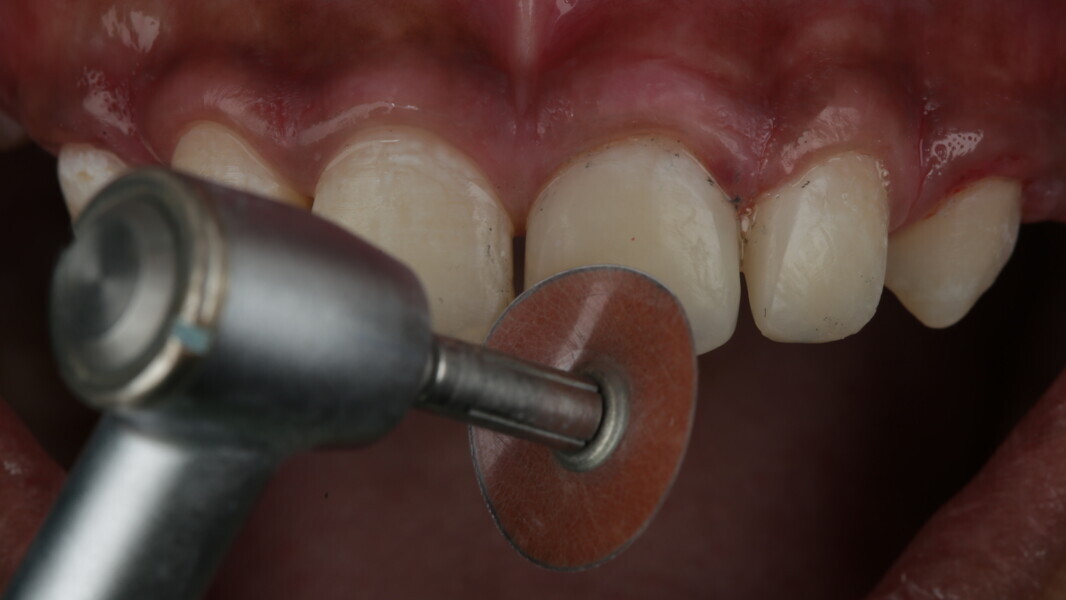

Fig 31-41: Polishing protocol and post-op